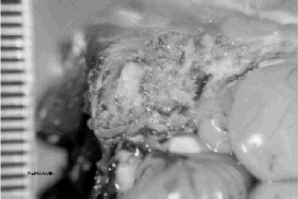

- Congestion, oedema and pus in the air space of the skull occurs in a proportion of affected birds due to secondary bacterial infections.

| Figure 10. Pus in skull bones. This is a common sequel to avian pneumovirus infection in both chickens and turkeys. |